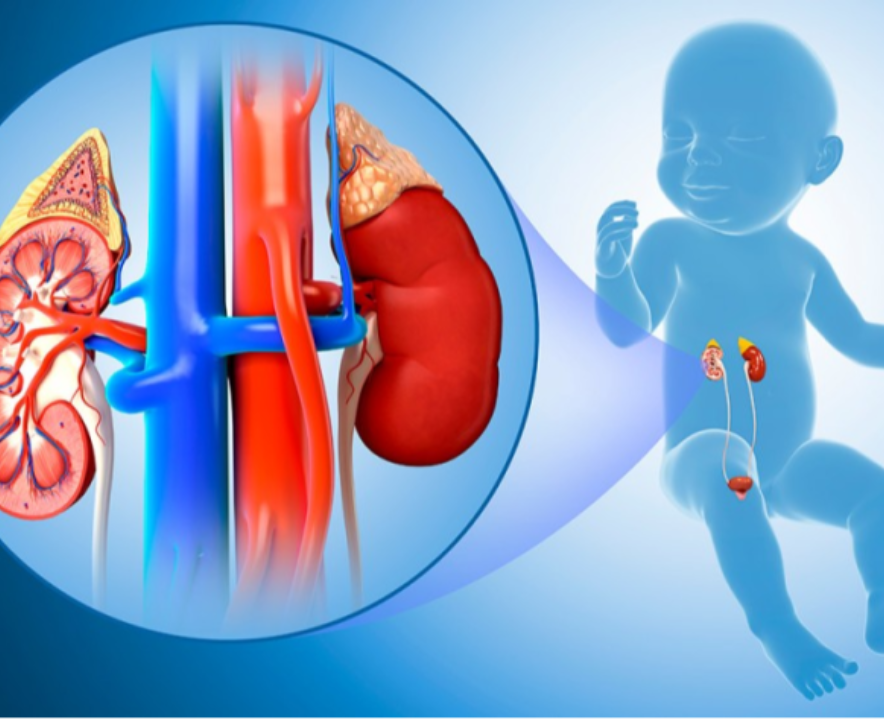

Pediatric urology is a subspecialty of urology that focuses on the diagnosis, treatment, and management of urologic conditions in children.

Read More